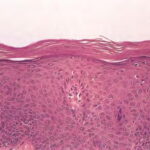

Pathologic findings in pityriasis rubra pilaris vary according to the duration of the disease. The findings are most likely to be diagnostic in the acute phase, when hyperkeratosis, acanthosis with broad short rete ridges, and alternating orthokeratosis and parakeratosis oriented in both horizontal and vertical directions can be observed (see Pityriasis Rubra Pilaris At a Glance). Usually, there is a sparse superficial, perivascular lymphocytic infiltrate in the underlying dermis. Keratinous plugs of the follicular infundibula as well as perifollicular areas of parakeratosis may also be present. A prominent granular layer and dilated, but not tortuous, capillaries are features that help to distinguish pityriasis rubra pilaris from psoriasis, the most important differential diagnosis.